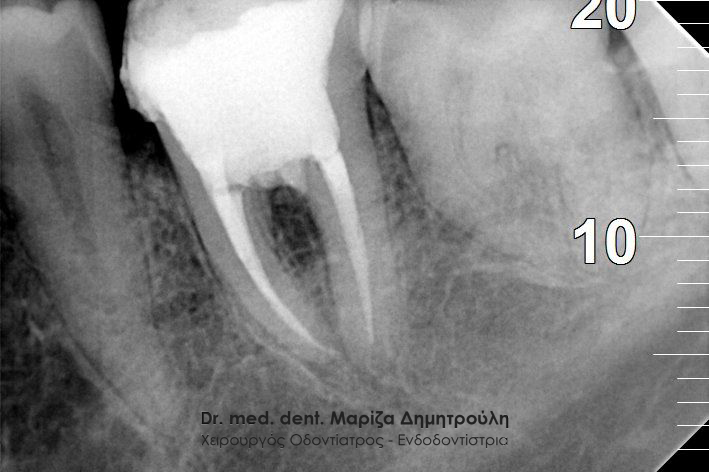

Μετά τη χορήγηση τοπικής αναισθησίας αφαιρέθηκε το παλιό σφράγισμα και εντοπίστηκαν οι ριζικοί σωλήνες του δοντιού (βλέπε φωτογραφία). Μετά την κατάλληλη επεξεργασία των ριζικών σωλήνων και εφόσον το δόντι ήταν ασυμπτωματικό η απονεύρωση ολοκληρώθηκε με την έμφραξη των ριζικών σωλήνων με ειδικό εμφρακτικό υλικό.

ΠΡΙΝ

ΜΕΤΑ